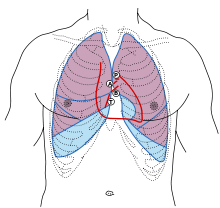

.svg.png)

Frontal view of the Aortic valve | |